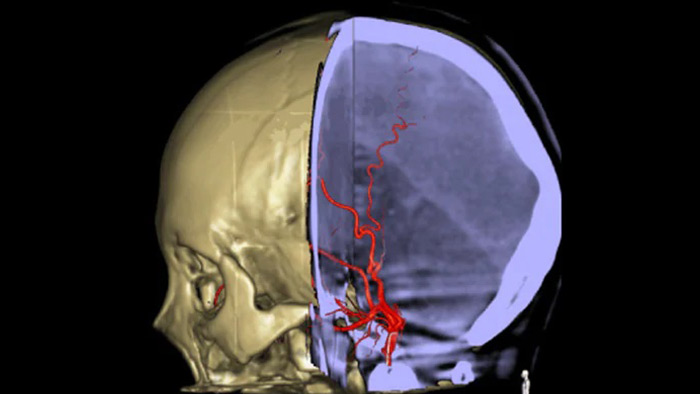

Tres SmartCT

Visualización similar a una TC

SmartCT Soft Tissue  genera una visualización de los tejidos blandos similar a la de una TC y apoya el diagnóstico del accidente cerebrovascular de tres maneras. Una exploración sin contraste ayuda a detectar los cambios isquémicos tempranos. Una exploración de fase temprana ayuda a identificar la oclusión proximal. Una exploración con contraste de fase tardía ayuda a detectar colaterales.

SmartCT Vaso IV

Comprobar la ubicación y la longitud del coágulo

SmartCT Vaso permite la visualización más allá del coágulo con imágenes periprocedimiento de las caras distales de los vasos en el accidente cerebrovascular isquémico. SmartCT Vaso es una técnica de adquisición basada en una TC de haz cónico y una inyección de contraste intrarterial. Permite la visualización más allá del coágulo con imágenes periprocedimiento de las caras distales de los vasos en el accidente cerebrovascular isquémico. Mediante el llenado retrógrado, se ven las estructuras de los vasos antes y después del coágulo. SmartCT Vaso 3D Roadmap puede utilizarse para visualizar los dispositivos de recuperación de coágulos.

Ver llenado colateral

Visualización del llenado colateral

La vista dual para ver los volúmenes de TC de haz cónico de fase temprana y tardía uno al lado del otro mejora la identificación de las áreas de penumbra y permite la visualización del relleno colateral.

Las referencias anatómicas apoyan una navegación 3D precisa

SmartCT

SmartCT Roadmap proporciona referencias anatómicas para apoyar la navegación precisa de la aguja guía, el catéter y el dispositivo al coágulo.